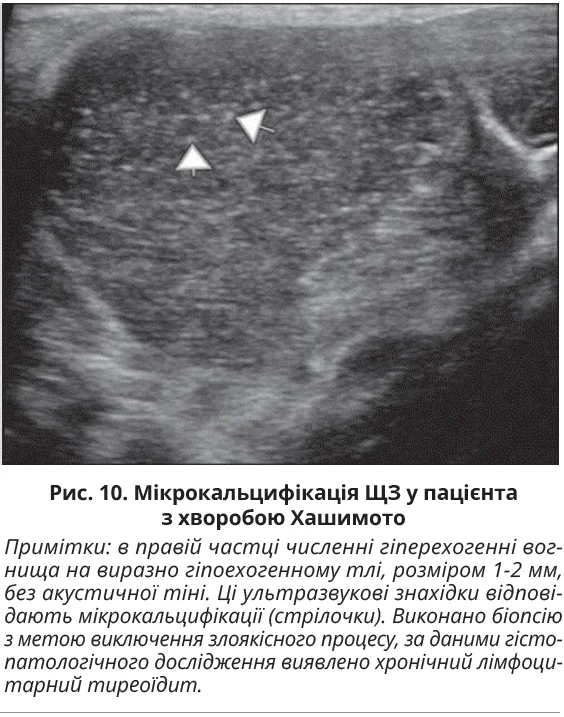

Дифузна мікрокальцифікація ЩЗ є одним із рідкісних проявів хвороби Хашимото. Мікрокальцифікати – це гіперехогенні вогнища діаметром 1-2 мм, які не дають задньої акустичної тіні. Наявність мікрокальцифікації є однією з патогномонічних ознак папілярного раку ЩЗ і потребує проведення тонкоголкової аспіраційної біопсії з подальшим цитологічним дослідженням для виключення злоякісного процесу. Мікрокальцифікація за хвороби Хашимото показана на рисунку 10.